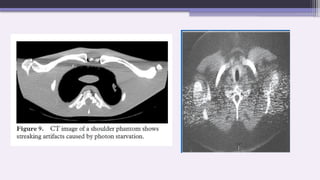

C. Photon starvation artifact

A potential source of serious streaking artifacts is photon

starvation, which can occur in highly attenuating areas such

as the shoulders.

When the x-ray beam is traveling horizontally, the attenuation is

greatest and insufficient photons reach the detectors.

The result is that very noisy projections are produced at these

tube angulations.

The reconstruction process has the effect of greatly magnifying

the noise, resulting in horizontal streaks in the image.

Appearance: